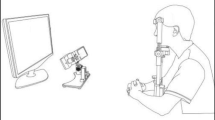

Setup

Eye movements were recorded in a dark and quiet room. Subjects were seated in an armchair with the head stabilized by a chinrest and a forehead contact. Visual stimulations were displayed on an Iiyama monitor located 57 cm in front of them (visual angle 56° × 35°). Horizontal and vertical eye movements were recorded with a video-based Eyetracker (Mobile EBT©, eyeBRAIN, www.eye-brain.com, France), at a sampling rate of 300 Hz. Each session started with a calibration procedure in which subjects were asked to look at a target presented at 13 successive locations. The oculomotor tasks were controlled by the MeyeParadigm software. Data were stored and analyzed subsequently with the MeyeAnalysis software (both softwares: www.eye-brain.com, France). Saccade onset and offset were automatically detected by a velocity threshold criterion and systematically controlled by the experimenter. Saccades with a latency below 90 ms or altered by blinks were discarded.

Oculomotor Tasks (Fig. 1)